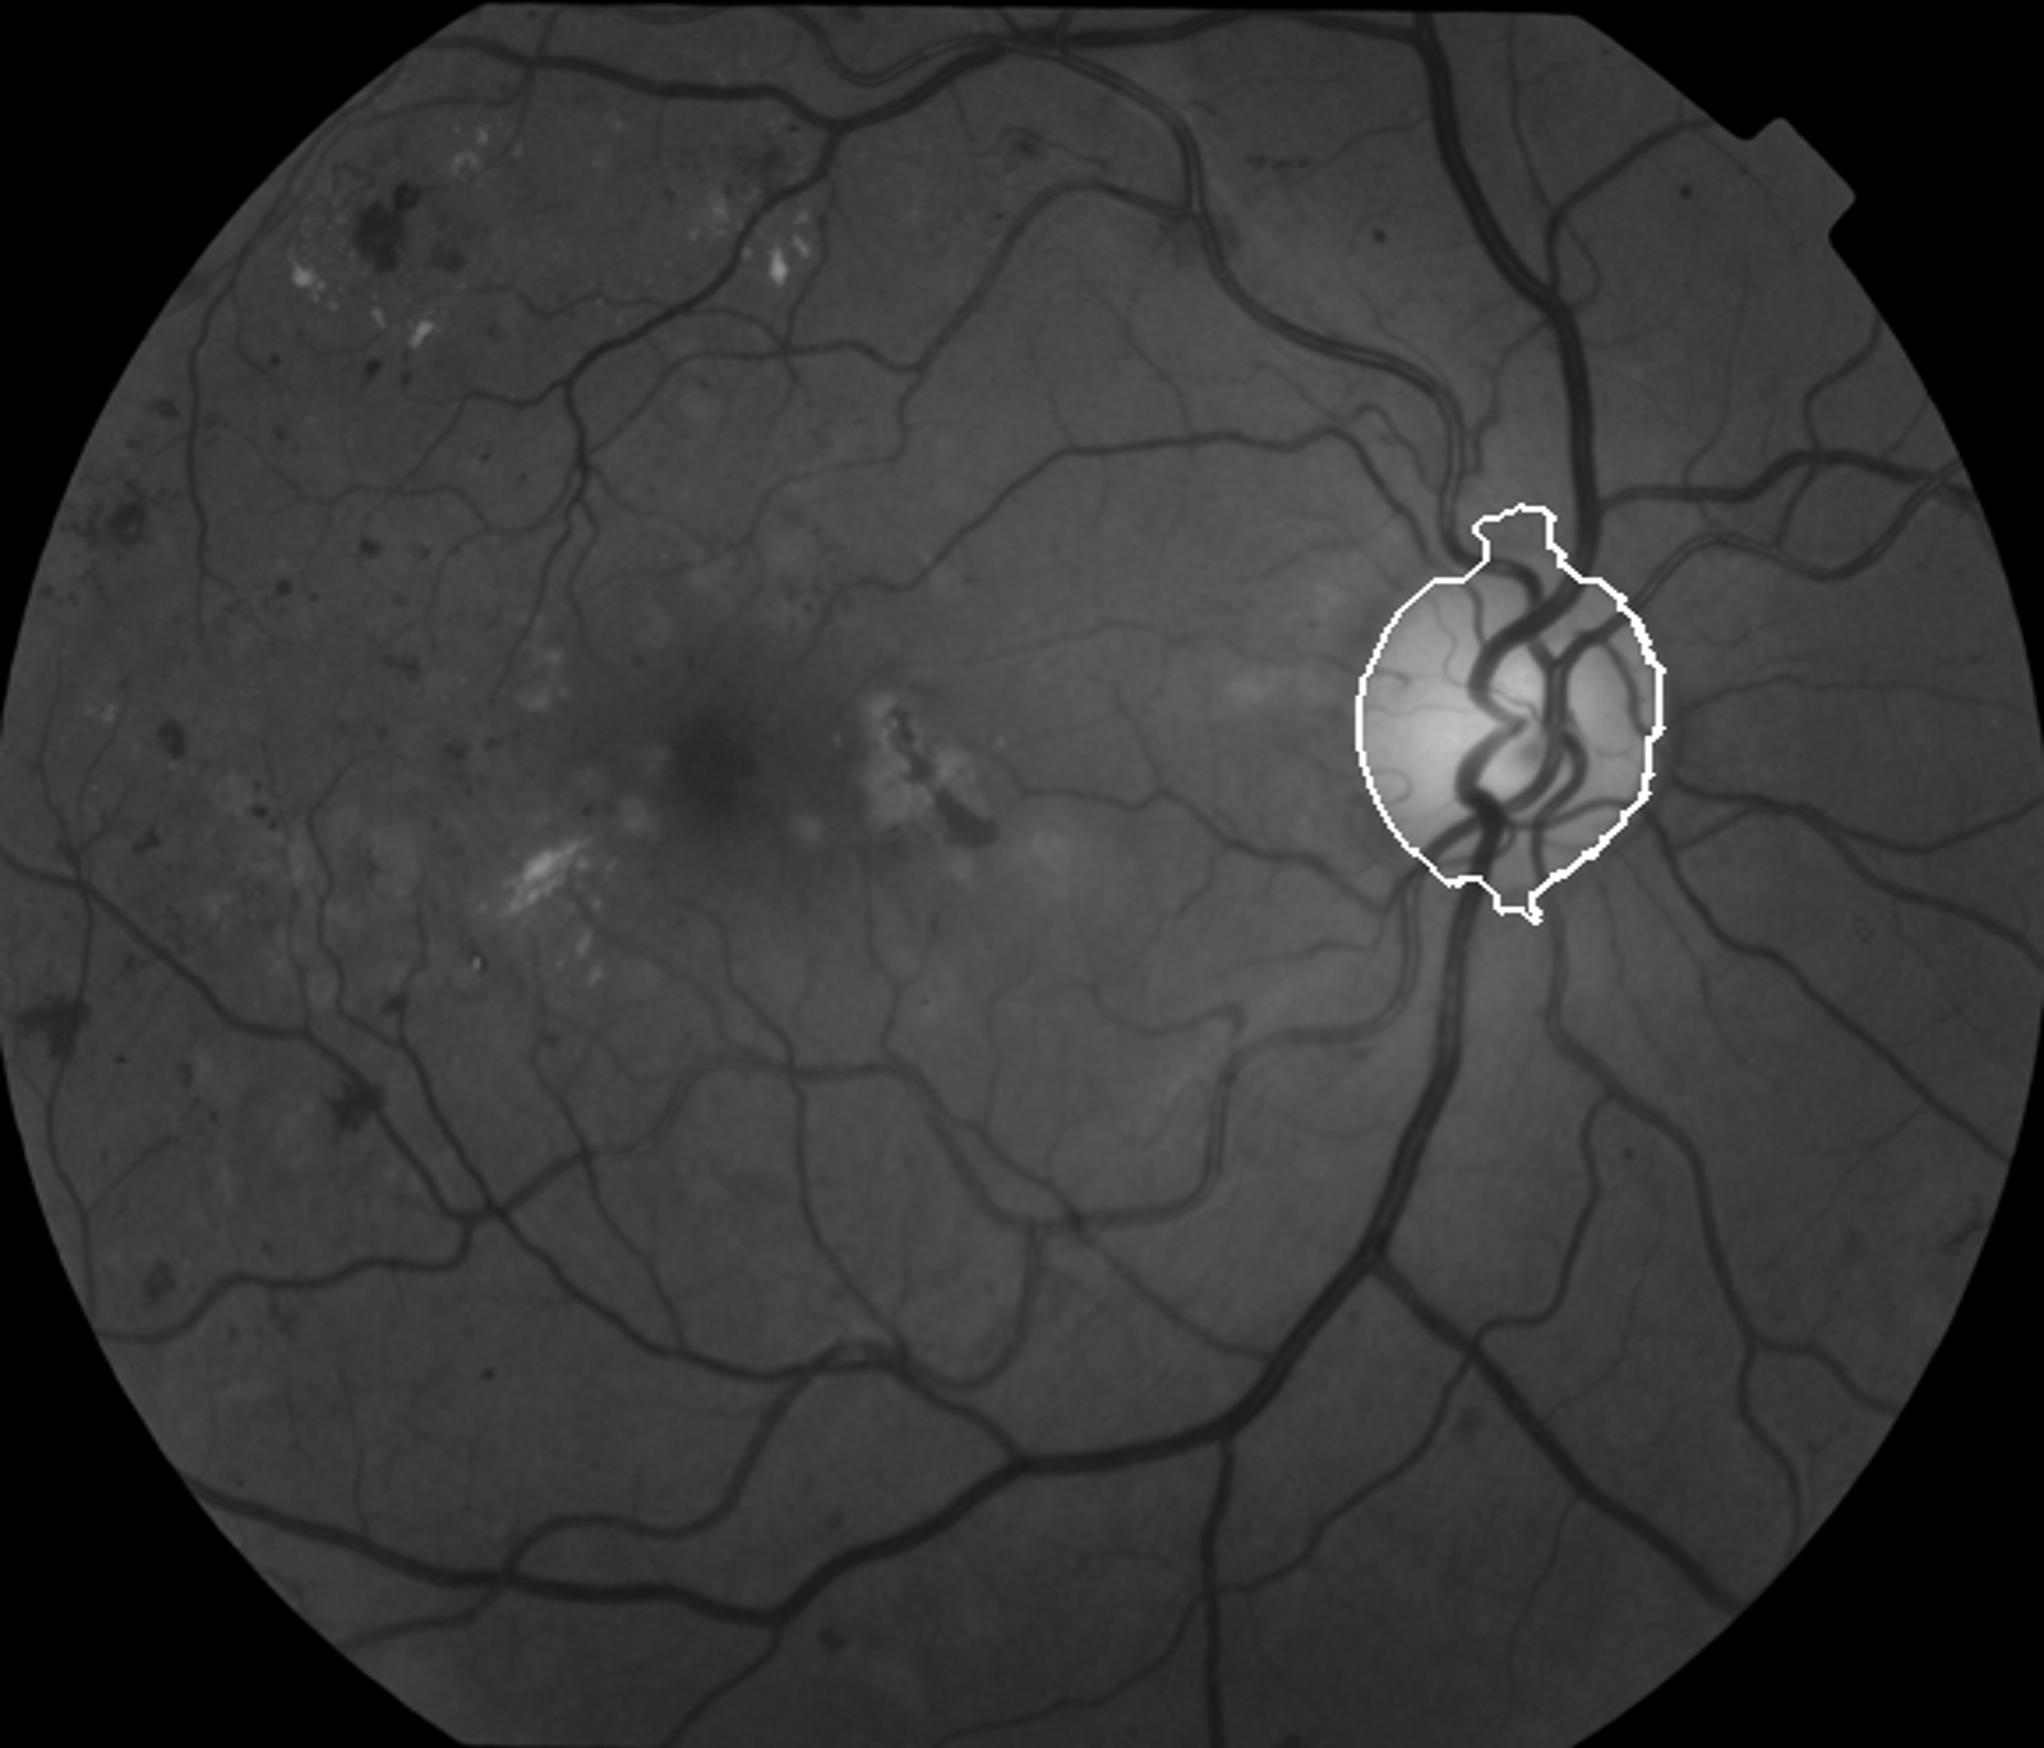

We applied our algorithm on 40 images of DRIVE dataset111http://www.isi.uu.nl/Research/Databases/DRIVE/and 50 images of Khatam database222Images of this database are gathered by Khatam-Al-Anbia eye hospital, Mashhad, Iran. In both datasets the optic disk boundary is hand labeled by an ophthalmologist as ground truth. Fig. 3 and Fig. 4 show our results on the DRIVE and Khatam databases respectively. The results show that our algorithm is robust to changing illumination and also to abnormal retinal images. The result on the second image of Khatam dataset (Fig. 3) shows that our algorithm can distinguish between parapapillary atrophy boundary and optic disk boundary.

In the next step, the average blood vessel width is computed in the window at the center of each connected component, as further describe in section . Then, the window with the highest average blood vessel width is selected as optic disk location. This value should be more than a fixed threshold, because in some cases, the optic disk area is not the brightest area of the retinal image. If no connected component has an average vessel width more than the defined threshold, we increase the threshold value of the first step and repeat the previous stages until circularity and average blood vessel width criterion are satisfied. Fig.1 shows how the optic disk area appears after increasing the threshold value.